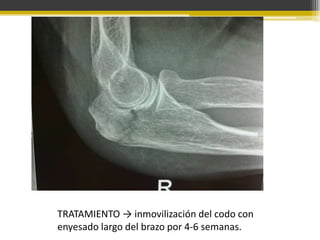

TRATAMIENTO → inmovilización del codo con

enyesado largo del brazo por 4-6 semanas.